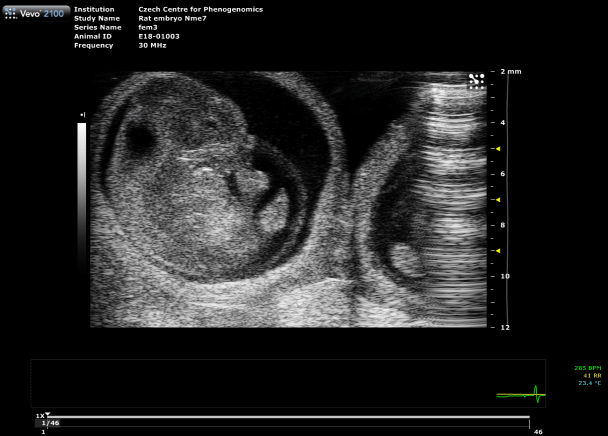

Fetal Echocardiography

For developmental studies, it is possible to monitor living mouse/rat embryos in uterus and follow the development of cardiac structures as well as changes in blood flow velocities in the heart and umbilical artery. An application of high-frequency probes with conventional 2D and pulse-wave Doppler imaging of the fetus can provide excellent information on the early development of cardiac structures.

Custom services Embryo Sonography (Fetal Sonography)

Gravidity check

Ultrasound confirms pregnancy in rodents from E6.5 onward, when external signs are not visible. We offer three levels:

- Standard – Basic check with 2D imaging.

- Counting – Check plus accurate embryo counting via 3D scan.

- Assessment – Full evaluation: vitality, counting, 3D imaging, Doppler.

Benefits: Early detection reduces animal use, prevents unnecessary euthanasia after miscarriage, and accelerates projects by enabling timely re-mating when pregnancy is not confirmed.